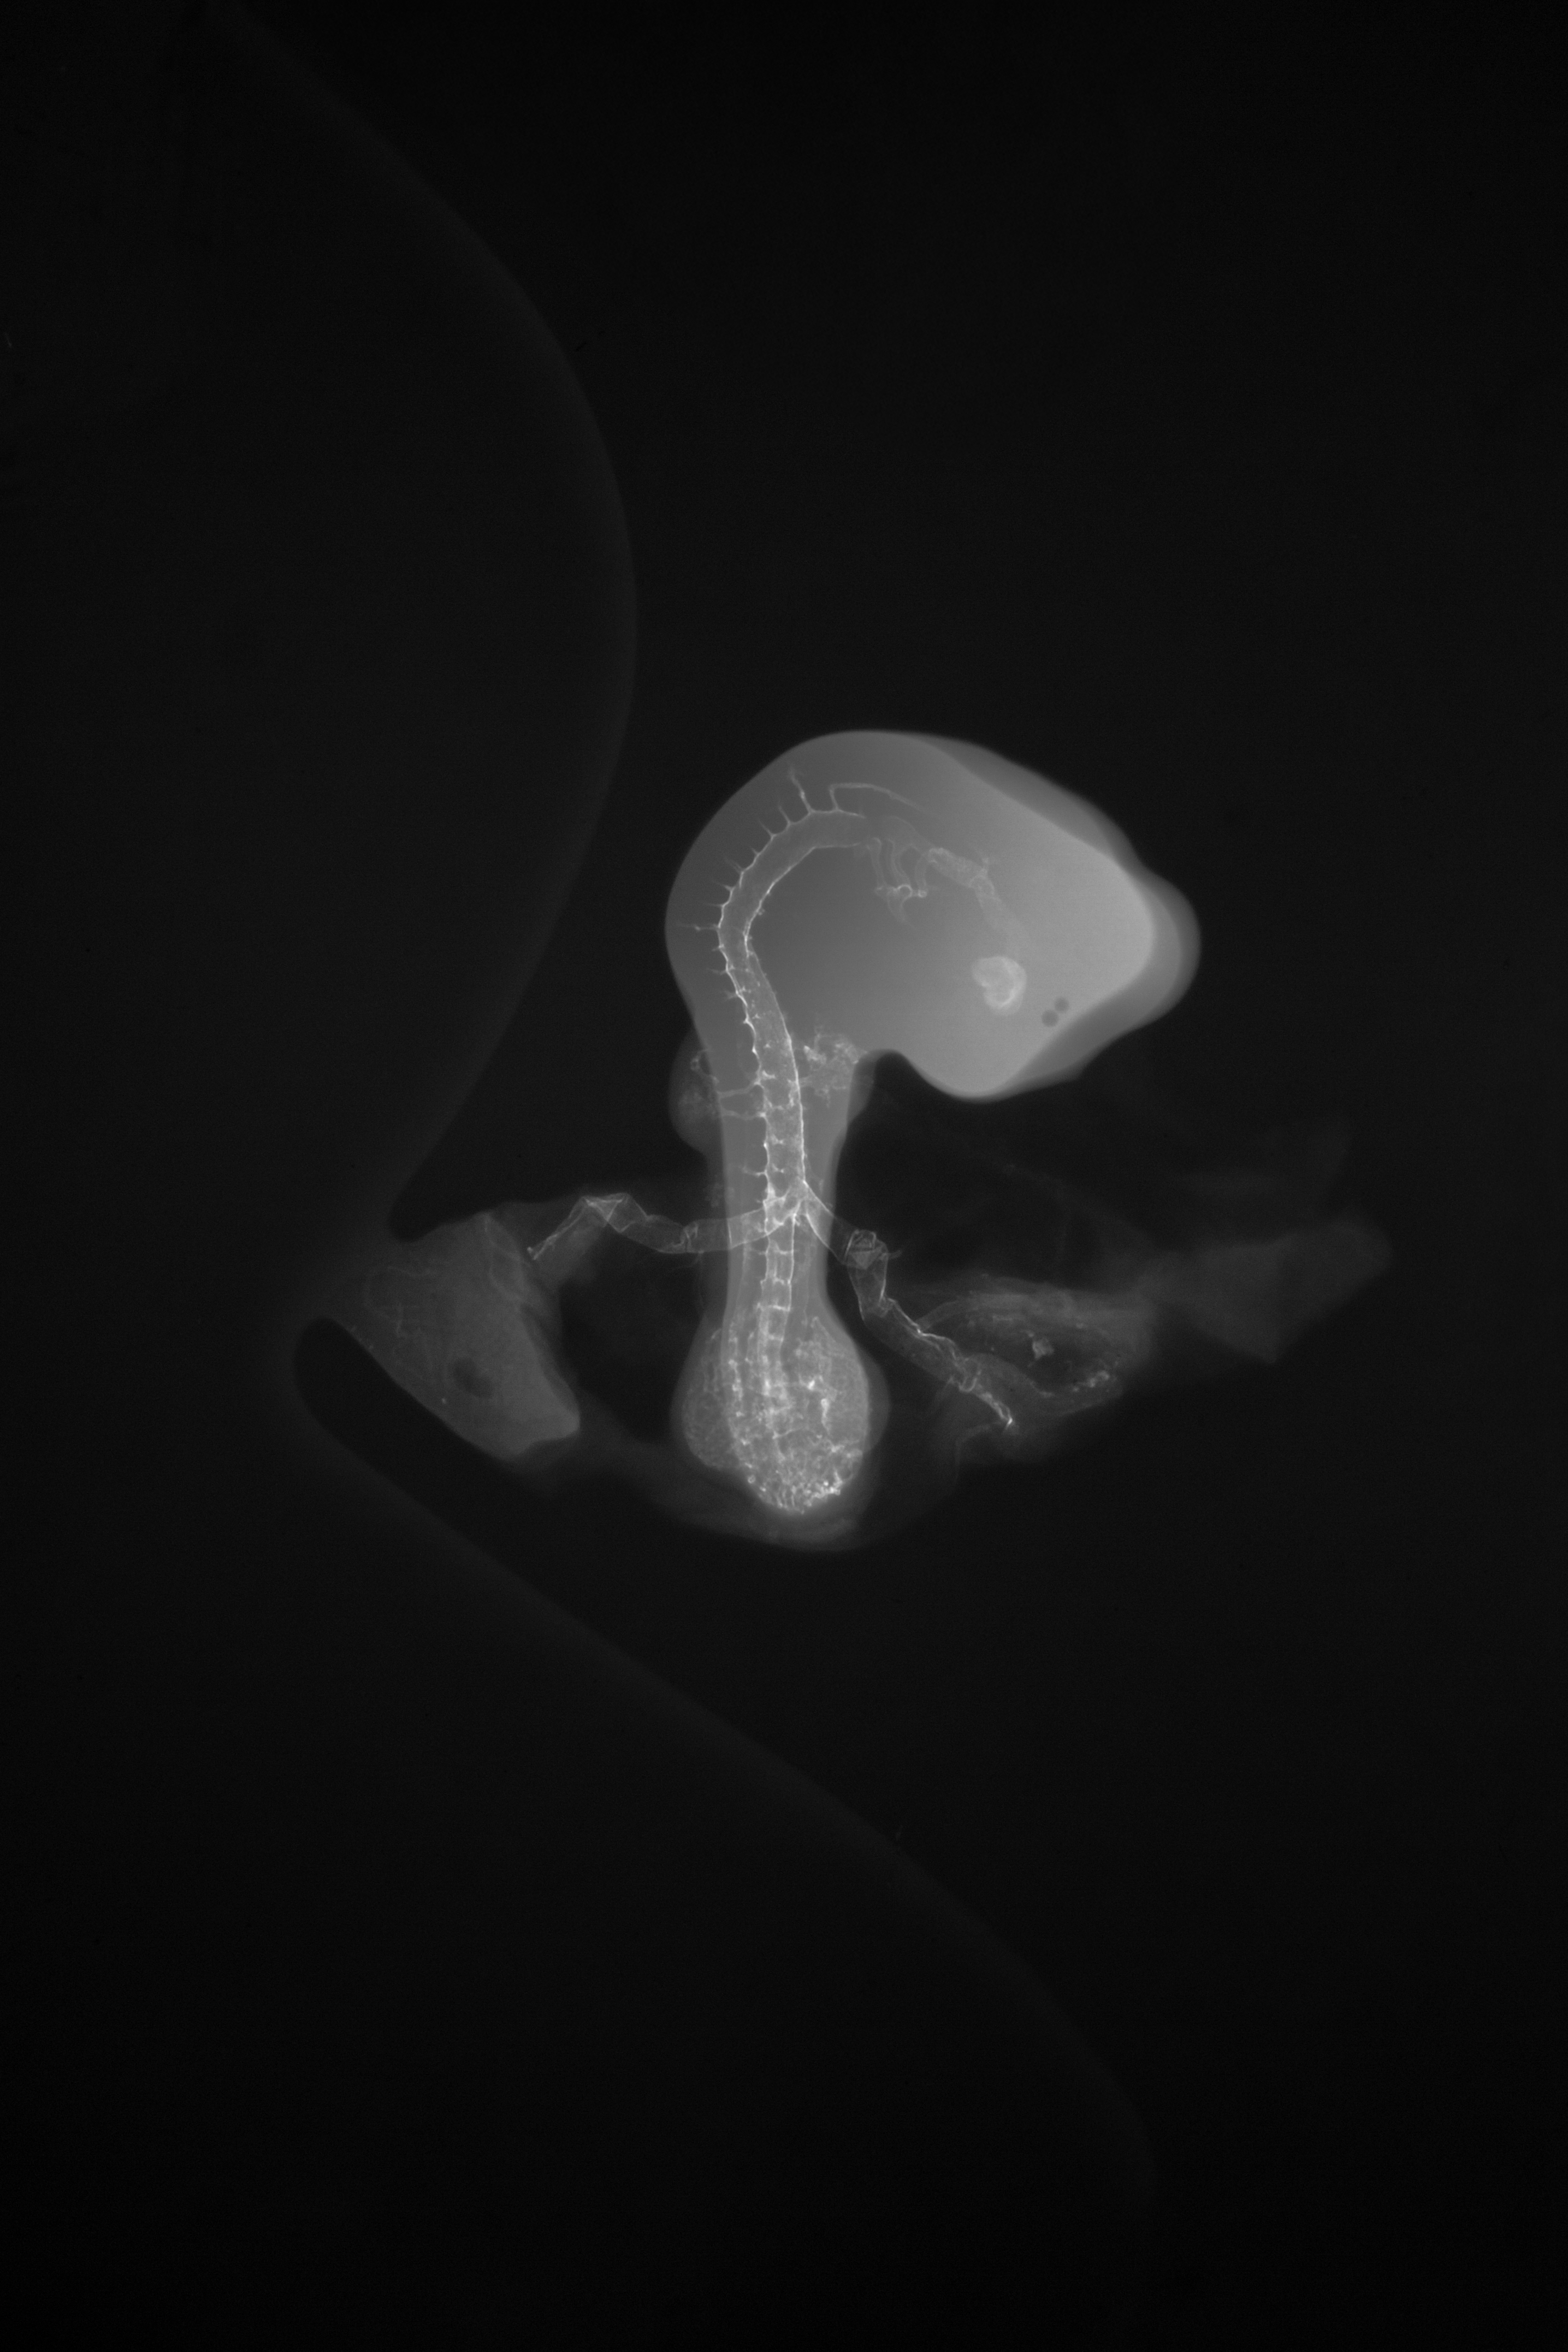

Chick Embryo Microangiography

Hamburger-Hamilton (HH) Stage 20 (approx. 3 - 3.5 days)

Stereo X-Ray Micrographs